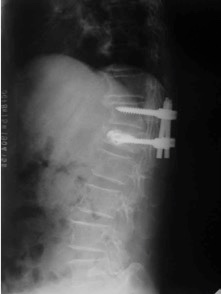

治疗:因患者椎体压缩骨折明显,椎体后缘骨折不完整,突入椎管,且硬膜囊受压,因此不适合行椎体成形术。给予单节段椎弓根钉固定并椎板切除减压术。骨折椎置钉结合钉道骨水泥加强稳定性。术后随访效果满意。

随访未见内固定松脱,无矫正丢失。